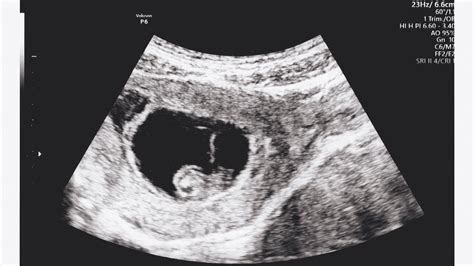

A 9. héten történő terhességi vizsgálatok közé tartozhat az első ultrahangvizsgálat, amelyet általában a hüvelybe bevezetett ultrahangfejjel végeznek. Ennek célja a terhesség tényének igazolása, a beágyazódás vizsgálata, a szívhang ellenőrzése és a szülés várható időpontjának meghatározása. Az orvos megállapíthatja, hogy egy vagy több magzat fejlődik.

Megkezdődik az ízületek és a csontok fejlődése, és a kialakuló izmok segítségével az embrió már végez mozgásokat. Bár ezek a mozgások ultrahangon már láthatóak lehetnek, az édesanya még nem érzi őket. A szemhéjak kifejlődtek, de össze vannak nőve, és csak a 27. hét körül nyílnak ki. A kis fülkagylók vonalai is látszanak. A szemek fejlődése befejeződött, de a szemhéjak össze vannak nőve. A kicsi fülcimpák már láthatóak, és a száj, orr és orrlyukak már jól elkülöníthetőek.